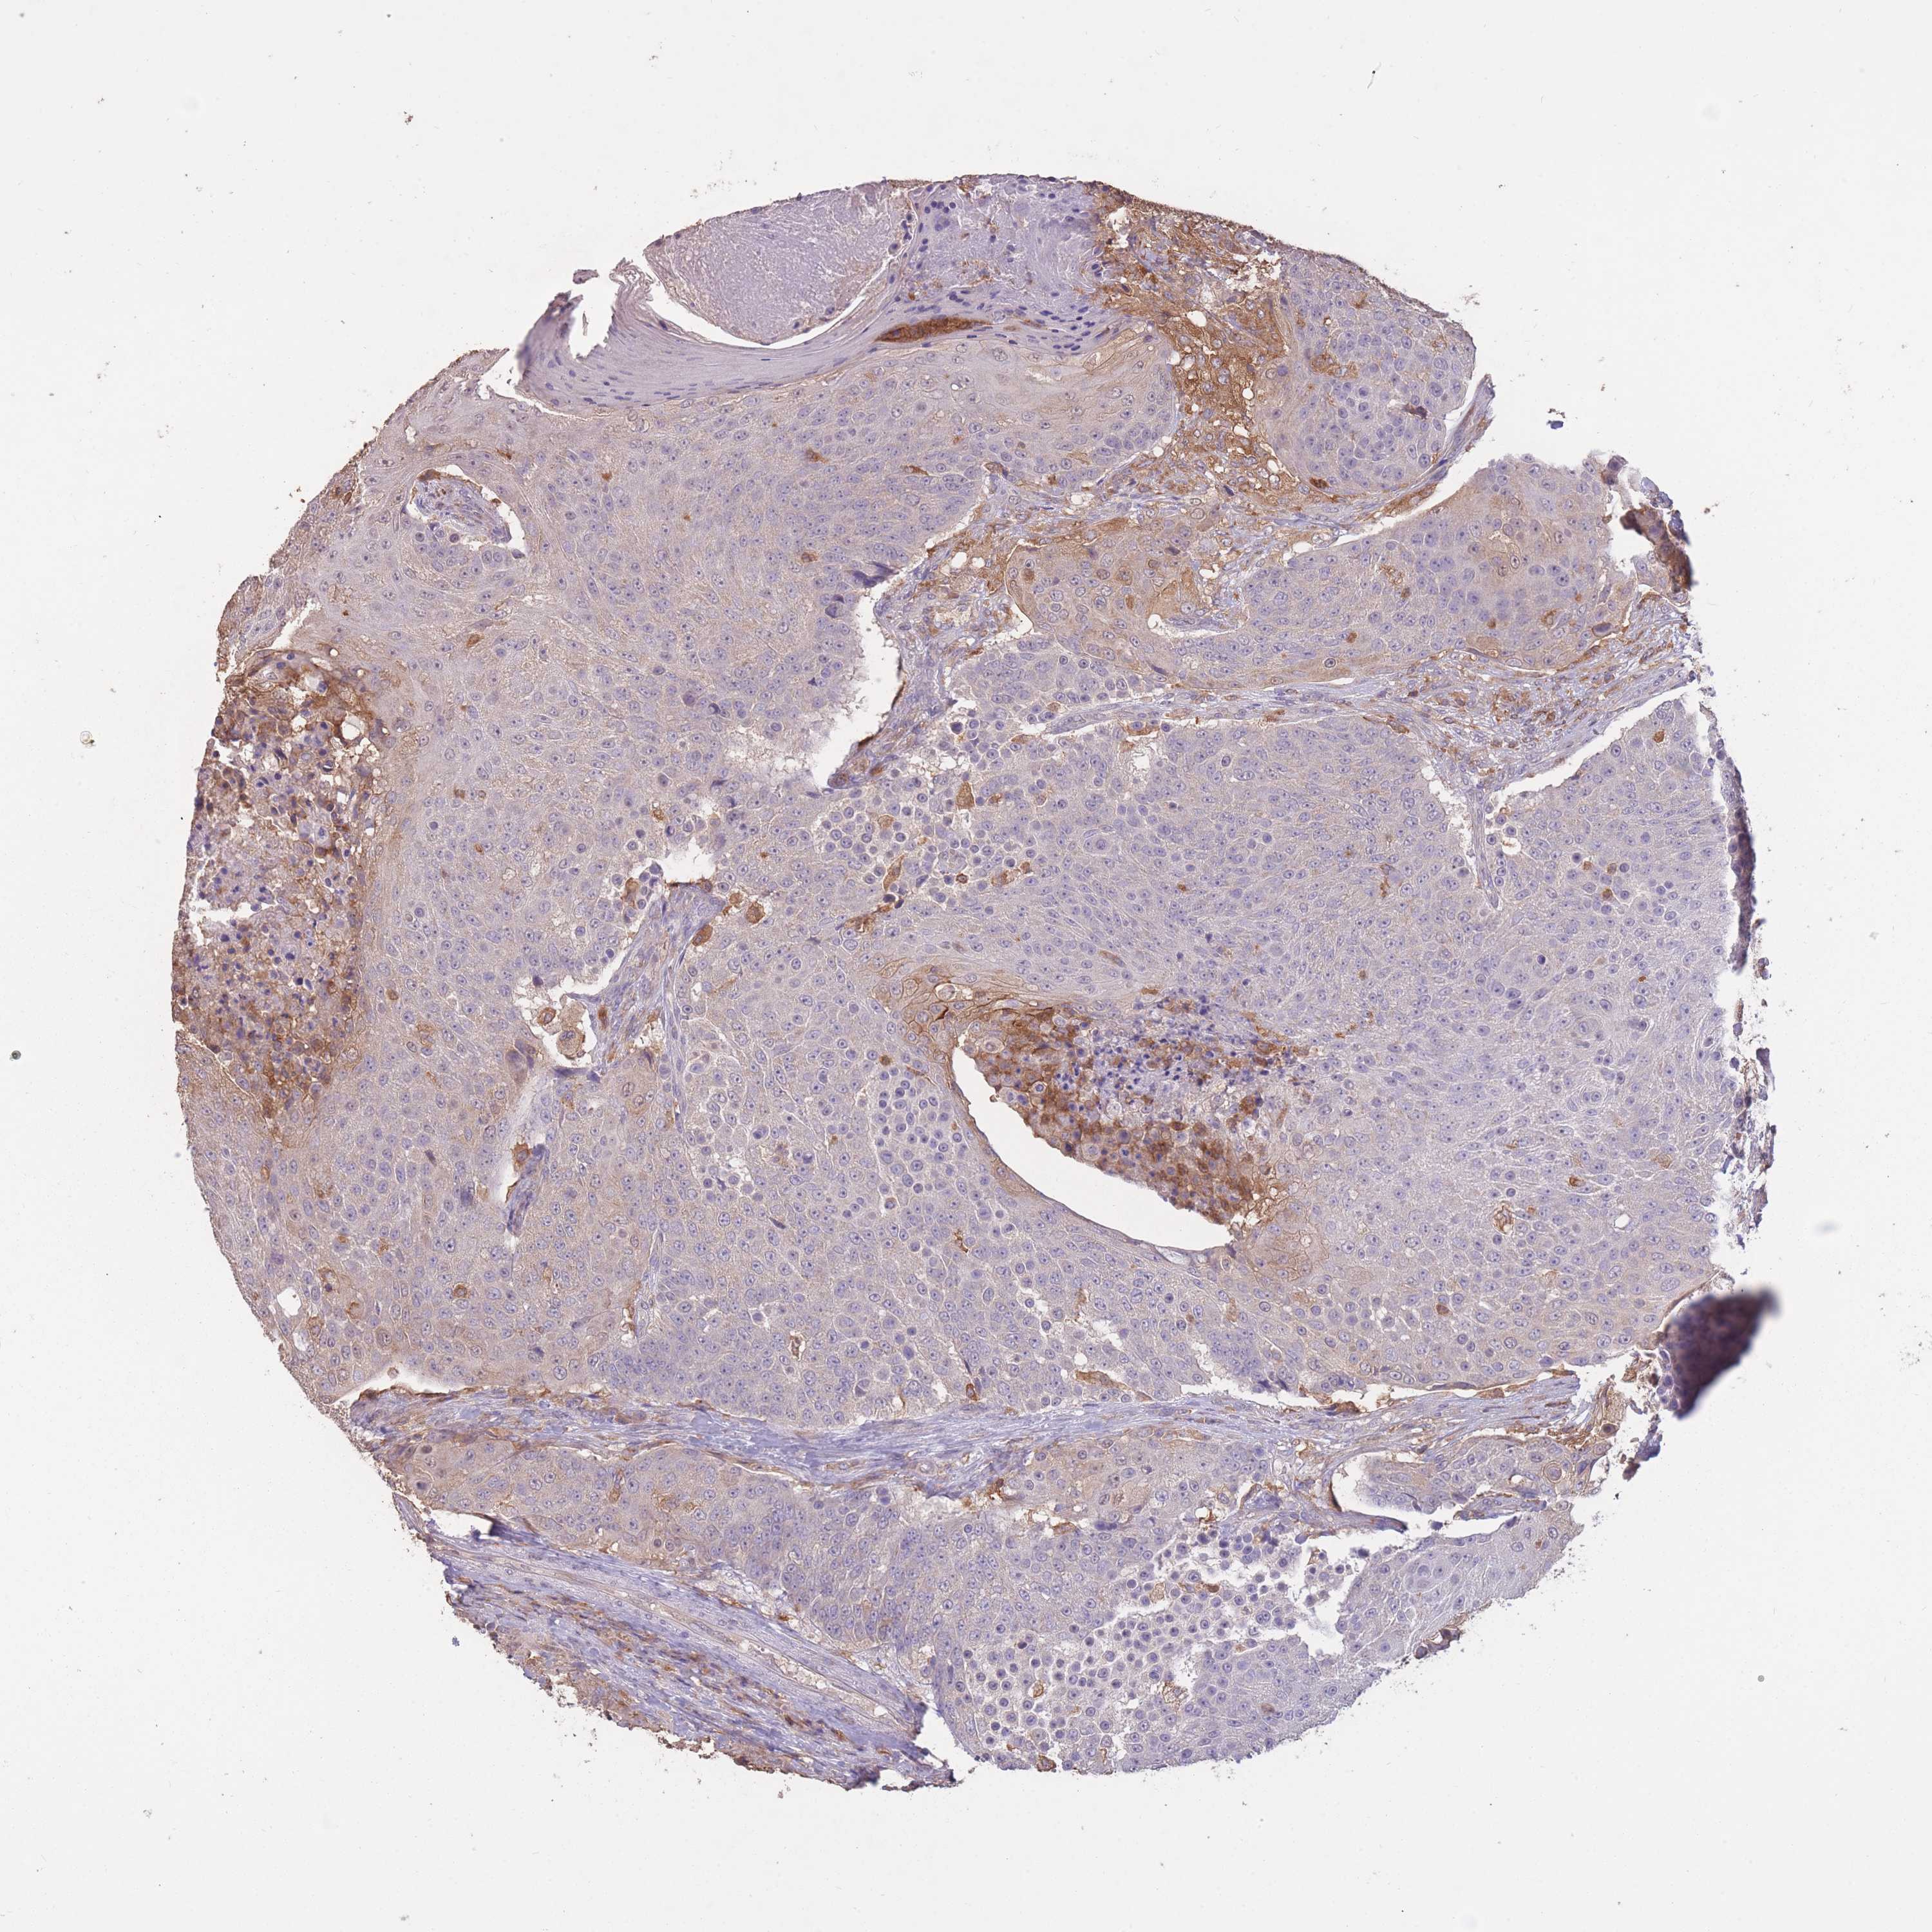

UROTHELIAL CANCER - Protein expressioni

A mouse-over function shows sample information and annotation data. Click on an image to view it in a full screen mode. Samples can be filtered based on level of antibody staining by selecting one or several of the following categories: high, medium, low and not detected. The assay and annotation is described here.

Note that samples used for immunohistochemistry by the Human Protein Atlas do not correspond to samples in the TCGA dataset.

Antibody stainingi

Antibody staining in the annotated cell types in the current human tissue is reported as not detected, low, medium, or high, based on conventional immunohistochemistry profiling in selected tissues. This score is based on the combination of the staining intensity and fraction of stained cells.

Each image is clickable and will lead to virtual microscopy that enables deeper exploration of all samples and also displays staining intensity scores, fraction scores and subcellular localization as well as patient and tissue information for each sample.

Antibody HPA042484

Antibody HPA045481

Staining

High

Medium

Low

Not detected

Intensity

Strong

Moderate

Weak

Negative

Quantity

>75%

75%-25%

<25%

None

Location

Nuclear

Cytoplasmic/membranous

Cytoplasmic/membranous,nuclear

Urothelial carcinoma, High grade

Urothelial carcinoma, Low grade

Urothelial carcinoma, NOS